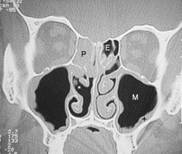

Da man sich als Laie schlecht vorstellen kann wo genau diese Nasenmuscheln in der Nase sitzen hier zusätzlich zu dem oberen Bild ein frontaler Querschnitt durch das Mittelgesicht:

Abb. 1   Abb. 2

Abb. 1: Hier relativ normale Verhältnisse. Die Nasenmuscheln lassen noch genügend Luft (schwarz) durch die Nasenhöhle strömen obwohl die Scheidewand leicht verkrümmt ist

Abb. 2: Auf der rechten Seite des Bildes sehen sie verdickte untere Nasenmuschel und seitlich daneben die Kieferhöhle (M). Die Nasenatmung ist hier einseitig stark eingeschränkt. Die dünnen schwarzen Linien stellen die noch verfügbare Nasenatmung links dar!

Erklärung: Schwarz: Luft, Graustufen: Weichteile, Weiß: Knochen, IT: untere Nasenmuschel, M: Kieferhöhle, S: Nasenscheidewand